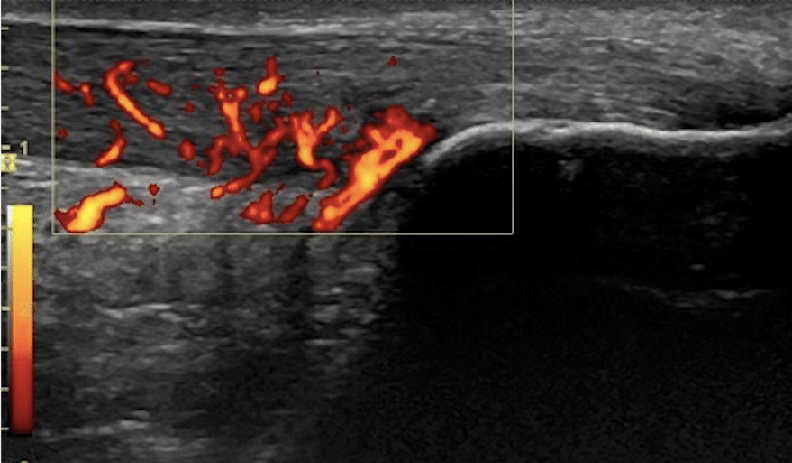

图:高定义多普勒下的血流增生

这张是纵向视图结合彩色多普勒血流的超声图:

大量异常血流(橘红色) 是慢性腱病的一个超声特征,特别是在中段型跟腱病中更明显。

它不等同于急性炎症的“经典炎症性充血”,但常提示慢性病变组织代谢活跃。